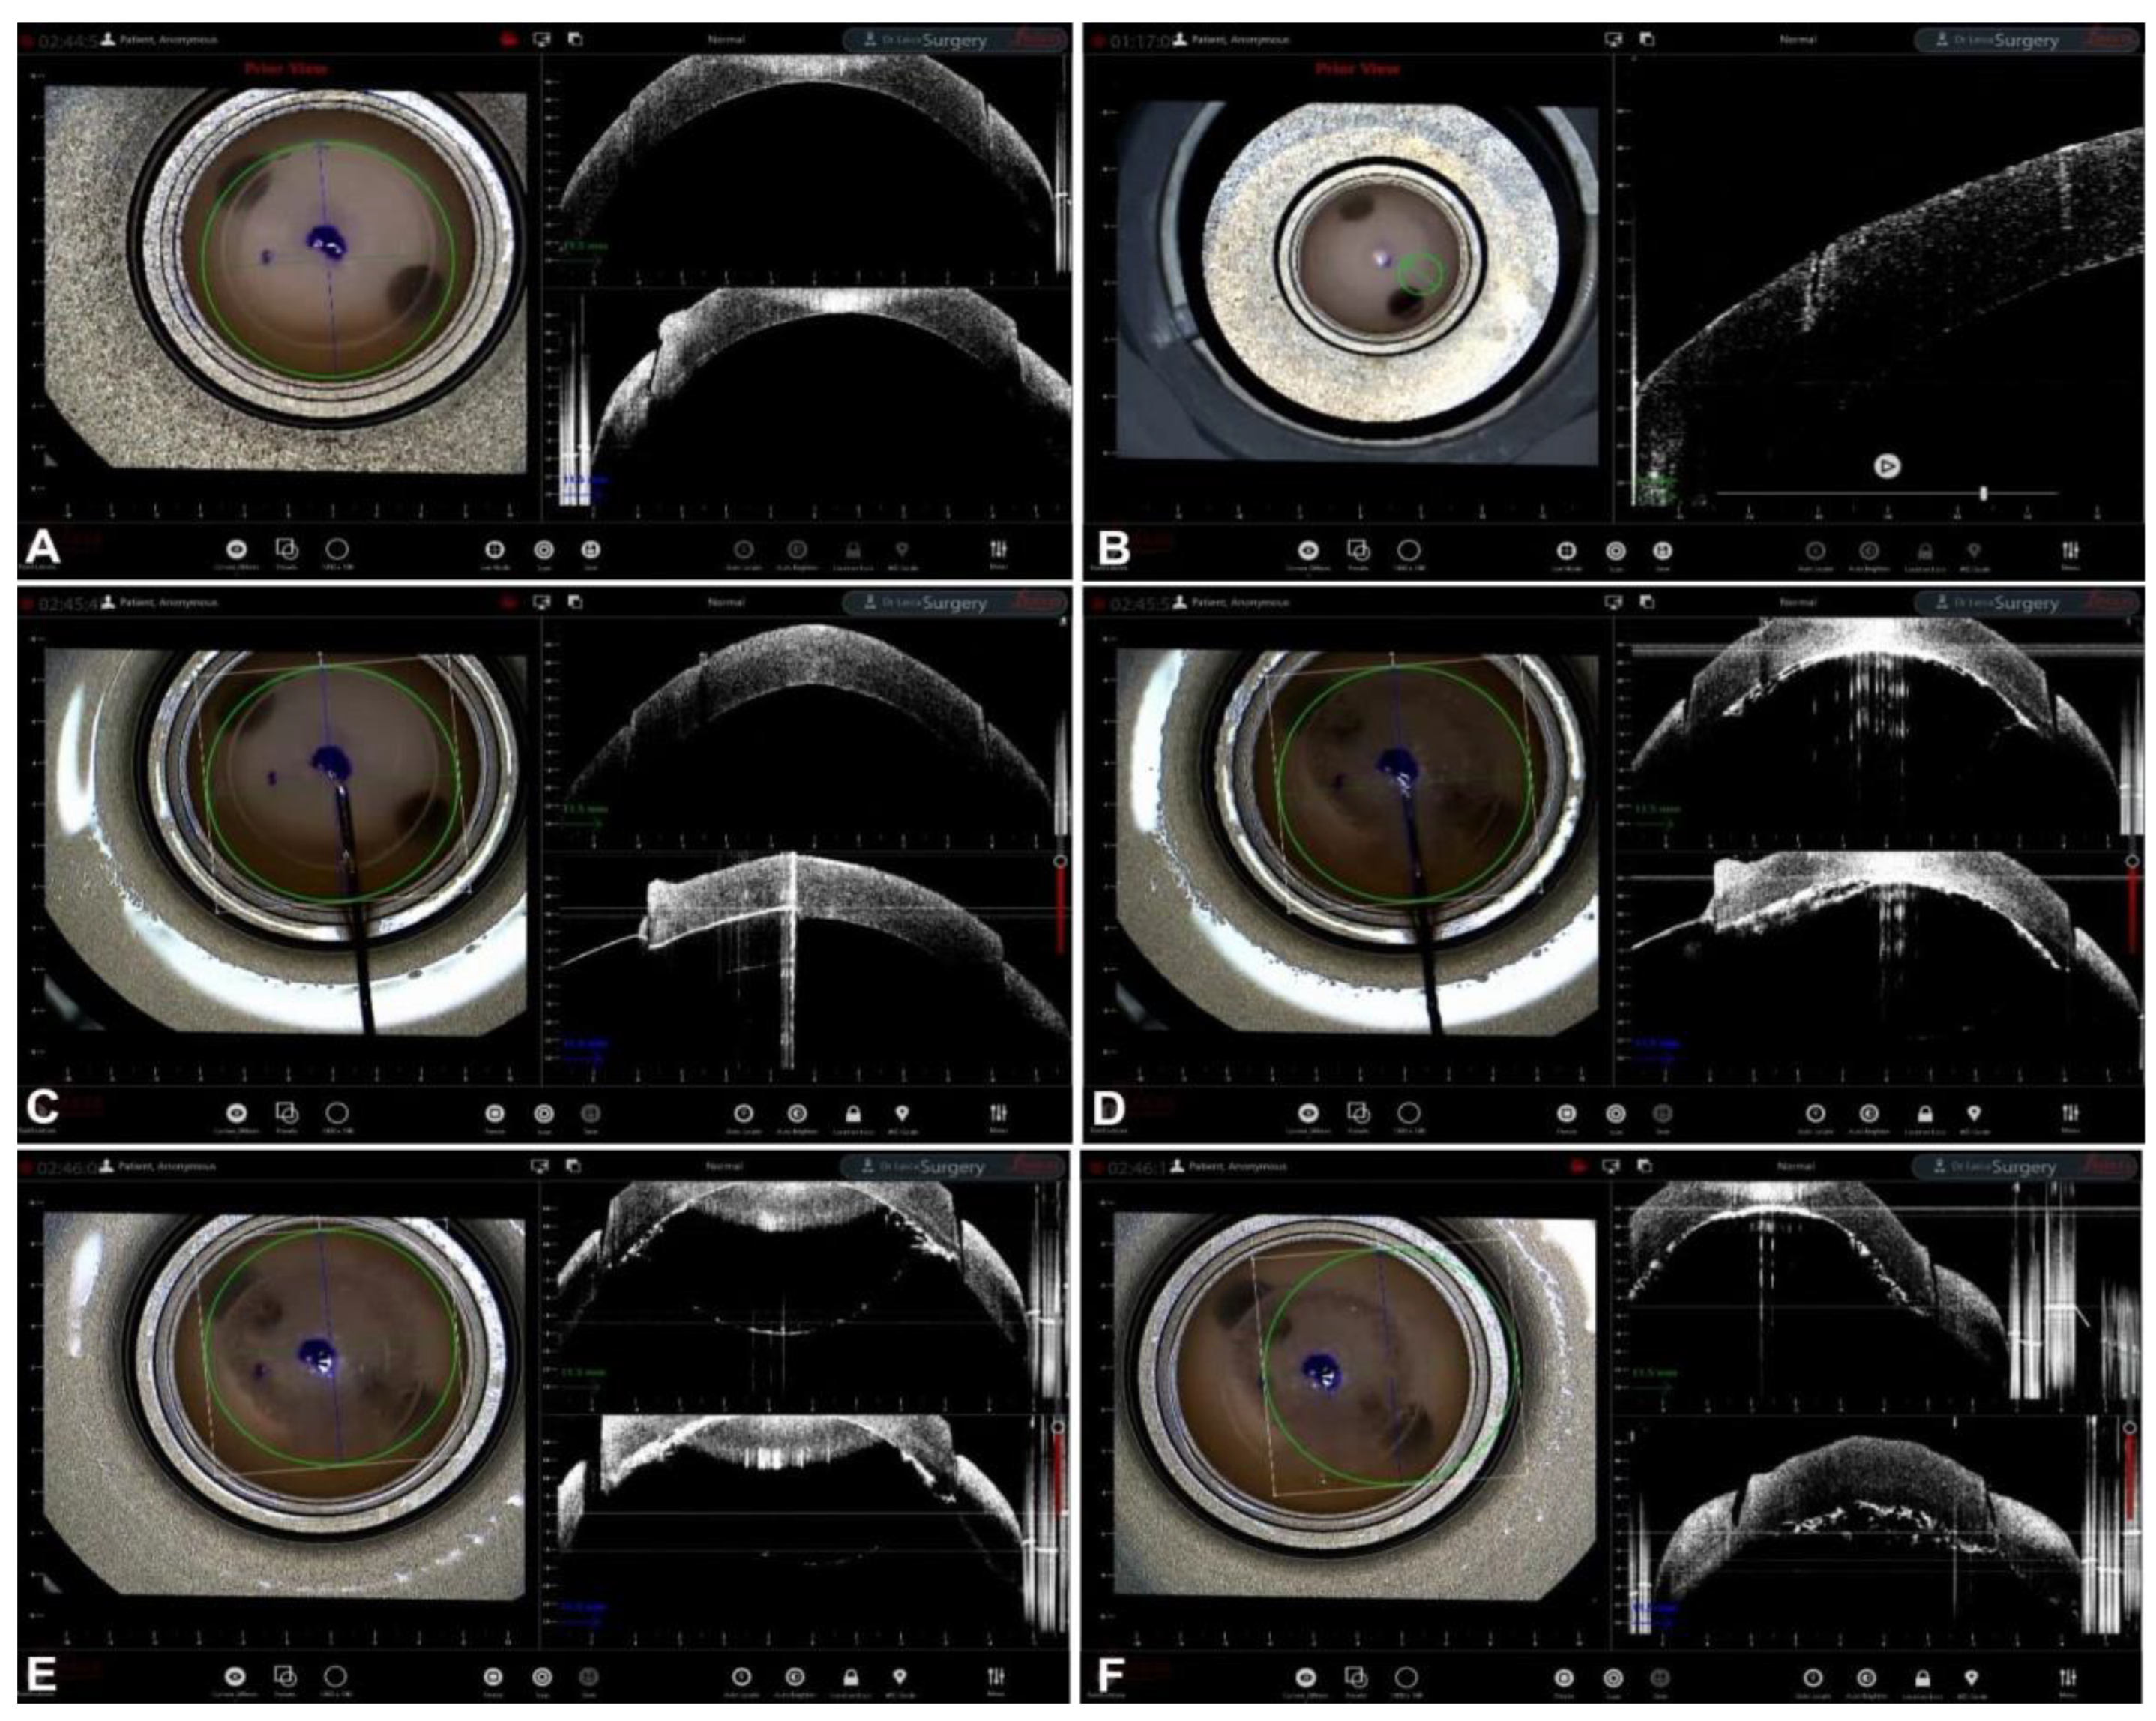

Guiding Big-Bubble Deep Anterior Lamellar Keratoplasty (BB-DALK)

3. Guiding Manual Stromal Dissection DALK

- Santorum, P.; Yu, A.C.; Bertelli, E.; Busin, M. Microscope-Integrated Intraoperative Optical Coherence Tomography–Guided Big-Bubble Deep Anterior Lamellar Keratoplasty. Cornea 2021, 41, 125–129. [Google Scholar] [CrossRef]

- Scorcia, V.; Busin, M.; Lucisano, A.; Beltz, J.; Carta, A.; Scorcia, G. Anterior Segment Optical Coherence Tomography–Guided Big-Bubble Technique. Ophthalmology 2013, 120, 471–476. [Google Scholar] [CrossRef] [PubMed]

- Myerscough, J.; Friehmann, A.; Busin, M.; Goor, D. Successful Visualization of a Big Bubble during Deep Anterior Lamellar Keratoplasty using Intraoperative OCT. Ophthalmology 2019, 126, 1062. [Google Scholar] [CrossRef] [PubMed]

- Altaan, S.L.; Termote, K.; Elalfy, M.S.; Hogan, E.; Werkmeister, R.; Schmetterer, L.; Holland, S.; Dua, H.S. Optical coherence tomography characteristics of different types of big bubbles seen in deep anterior lamellar keratoplasty by the big bubble technique. Eye 2016, 30, 1509–1516. [Google Scholar] [CrossRef] [PubMed]

- Steven, P.; Le Blanc, C.; Lankenau, E.; Krug, M.; Oelckers, S.; Heindl, L.M.; Gehlsen, U.; Huettmann, G.; Cursiefen, C. Optimising deep anterior lamellar keratoplasty (DALK) using intraoperative online optical coherence tomography (iOCT). Br. J. Ophthalmol. 2014, 98, 900–904. [Google Scholar] [CrossRef] [PubMed]

- Au, J.; Goshe, J.; Dupps, W.J.; Srivastava, S.K.; Ehlers, J.P. Intraoperative Optical Coherence Tomography for Enhanced Depth Visualization in Deep Anterior Lamellar Keratoplasty from the PIONEER Study. Cornea 2015, 34, 1039–1043. [Google Scholar] [CrossRef]